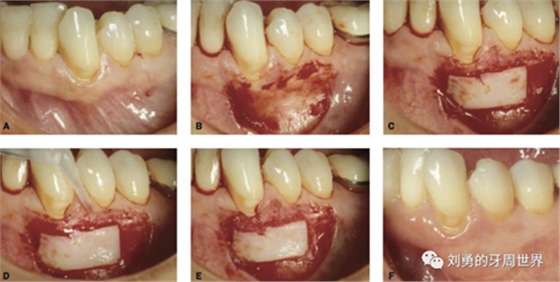

下面是上皮-結締組織聯(lián)合strip技術

如下圖:

可見右上前牙植體頰側無附著齦

為了減少取瓣大小,從上腭取厚一點的齦瓣,然后用刀片平行于表皮表面將齦瓣片切成兩個厚度一致的齦瓣,然后進行移植,這樣切成的兩個齦瓣一個有表皮,一個沒有表皮是單純的結締組織。如此的片切可以使齦瓣變成雙倍的大小使用,減少了供區(qū)的取瓣面積。